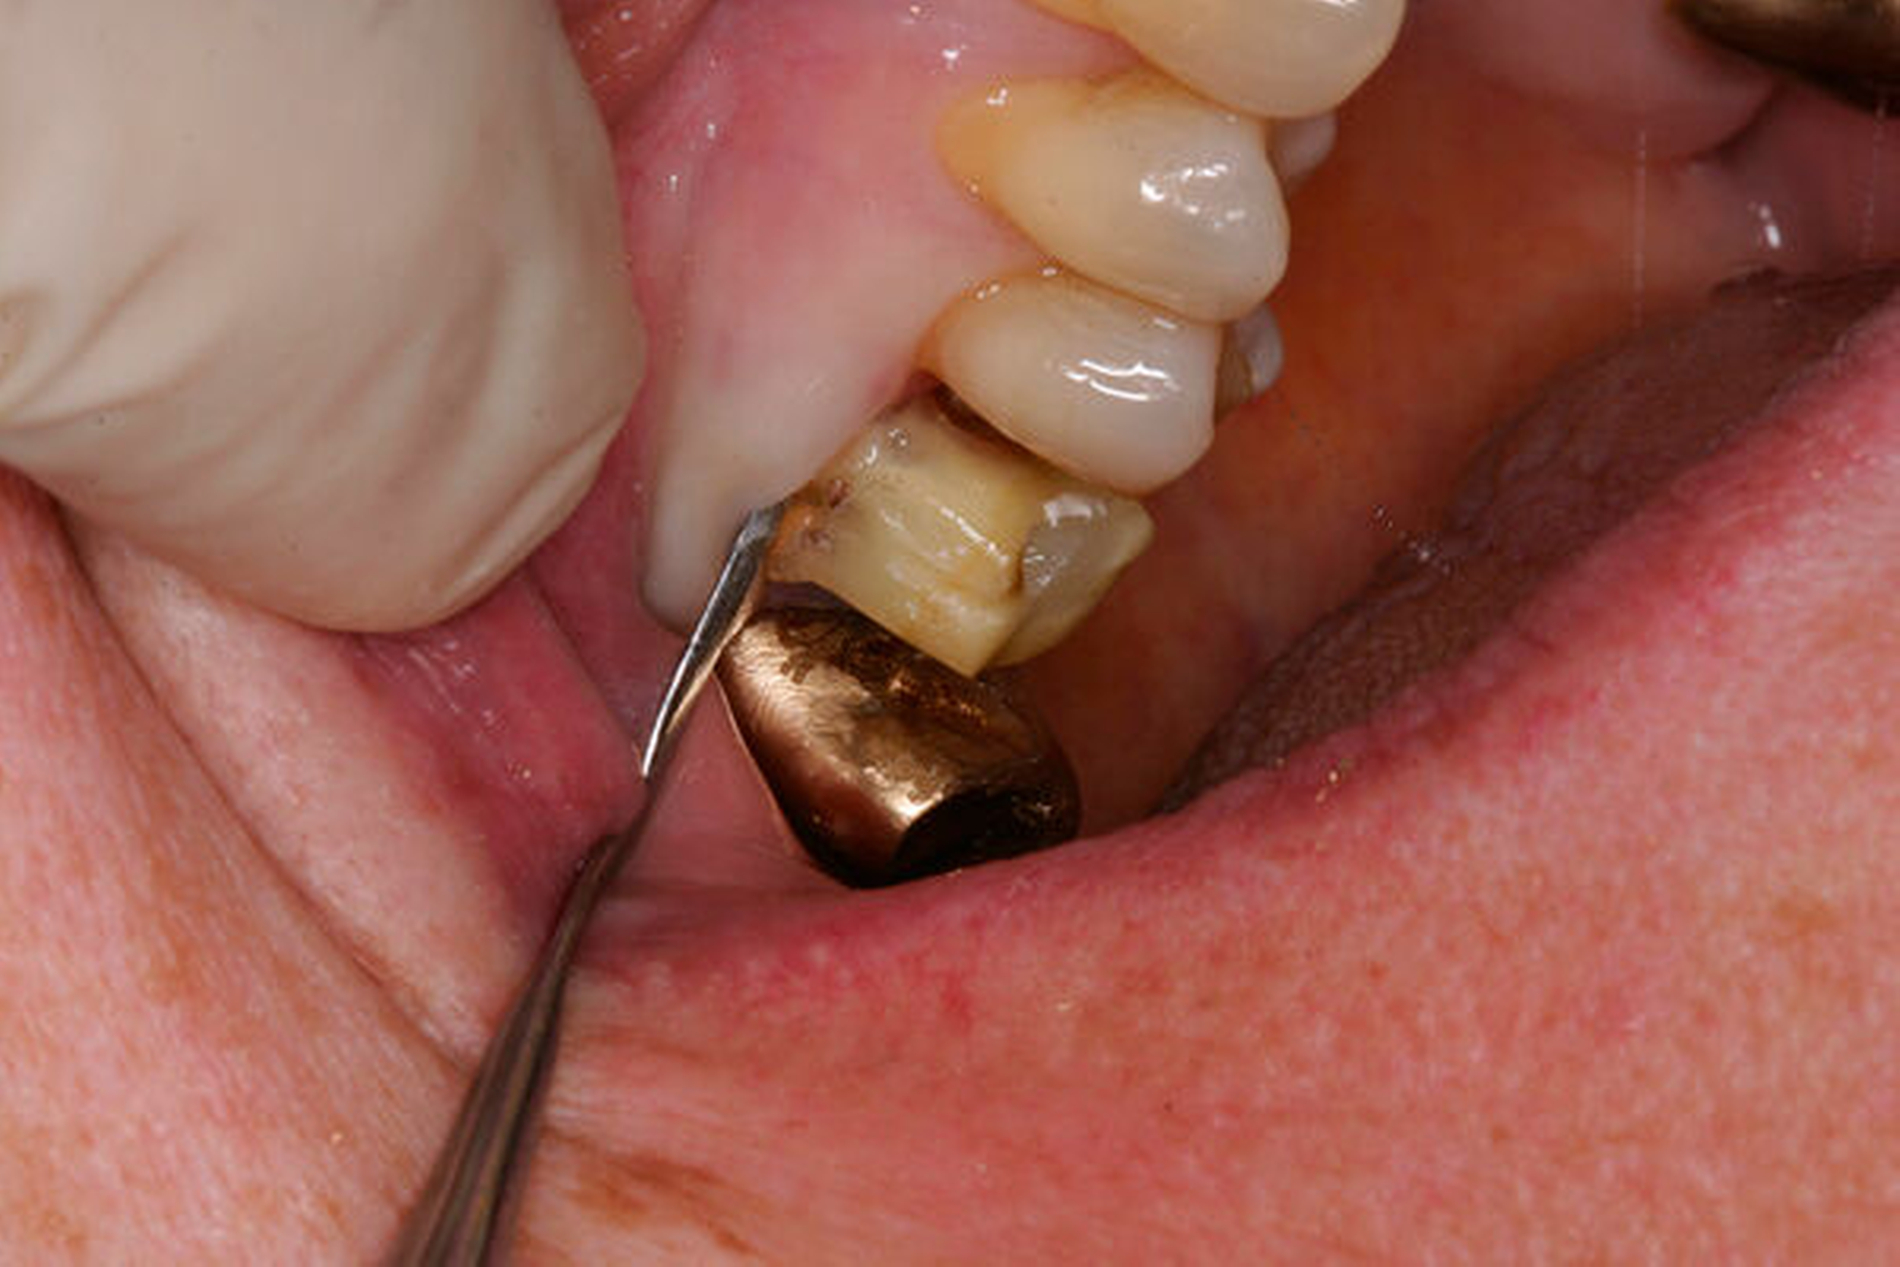

Nach der Anästhesie erfolgt bei einer beabsichtigten Entfernung einer der beiden bukkalen Wurzeln ein Ertasten der vestibulären Furkation. Wir halten es für ratsam, von der Furkation nach okklusal eine deutlich sichtbare Markierung mit einem wasserfesten Stift anzuzeichnen und diese Linie okklusal halbkreisförmig um die zu entfernende Wurzel zu verlängern. Das erleichtert die Orientierung beim Absetzen des zu entfernenden Zahnanteils. (Abbildung 1a).

Anschließend verwenden wir eine Lindemannfräse (H162SL, Firma Komet Dental, Lemgo) in einem Schnelllaufwinkelstück und trennen die Wurzel mitsamt des Kronenanteils vorsichtig entlang der zuvor angezeichneten Linie ab. Um den zu erhaltenden Zahnanteil nicht unbeabsichtigt mit der Fräse zu beschädigen, bleibt die Orientierungslinie zunächst unangetastet (Abbildung 1b).

Danach werden zunächst die dentogingivalen und die koronalen dentoalveolären Parodontalfasern der separierten Wurzel mit einem Periotom durchtrennt, anschließend wird die Wurzel mit Hebeln und Luxatoren gelockert. Falls erforderlich erfolgt die endgültige Entfernung mit einer Oberkiefer-Bajonettzange (Abbildung 1c).